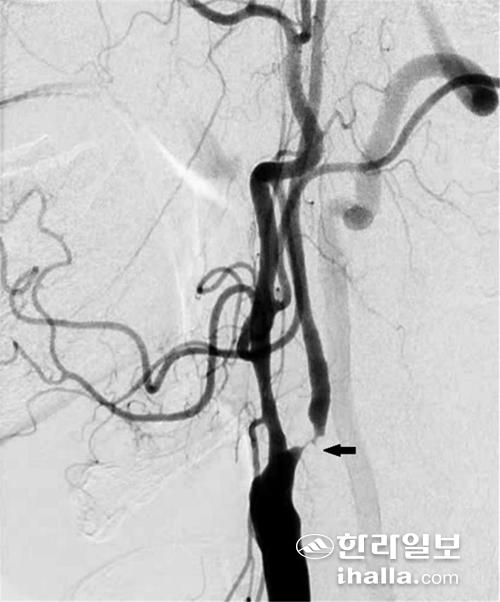

경동맥 협착증의 진단을 위한 비침습적인 검사로는 경동맥 초음파 및 CT, MRI를 이용한 혈관조영술이 있고, 침습적인 검사로는 뇌혈관 조영술 (transfemoral cerebral angiography)이 있다. 이 중 뇌혈관 조영술은 경동맥 협착증의 진단에 있어 가장 정확한 검사 중 하나로, 경동맥 재개통을 고려하는 환자들에게 널리 행해지고 있다.

경동맥 스텐트 삽입술은 대퇴동맥으로 관을 삽입해 경동맥 협착증이 있는 부위에 스텐트라는 금속 그물망을 펼쳐 좁아진 혈관을 넓혀주는 방법이다. 예전에는 경동맥 스텐트 삽입술이 주로 전신마취 하에 수술하기가 위험한 환자 및 경동맥 협착 부위가 너무 머리 쪽으로 높게 위치하고 있어 경동맥 내막절제술을 받기 힘든 환자들에게 선택적으로 행해졌다.

그러나 최근 들어 발표된 여러 논문에 따르면, 경동맥 스텐트 삽입술과 경동맥 내막절제술을 비교했을 때, 뇌졸중 예방 효과 및 안전성(합병증 발생 비율)에 있어 두 치료 방법이 비슷한 결과를 보였다.

이러한 결과를 바탕으로 미국, 유럽뿐만 아니라 우리나라에서도 경동맥 스텐트 삽입술을 시행하는 빈도가 점차 늘어 현재는 경동맥 내막절제술보다 더 많이 행해지고 있다. 경동맥 내막 절제술과 경동맥 스텐트 삽입술은 각각의 장·단점을 가지고 있으므로, 경동맥 재개통이 필요한 경동맥 협착증 환자의 경우 전문의와 상의해 환자에게 적절한 치료 방법을 결정하는 것이 좋겠다.